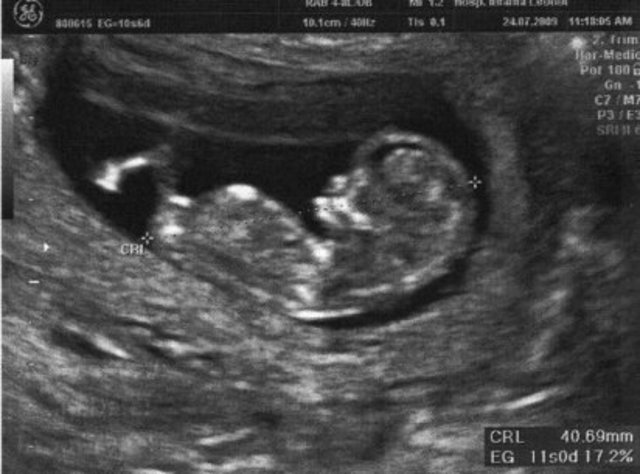

• Semana 11

Semana 11

El esqueleto, hasta ahora constituido únicamente de cartílago, acoge ahora las primeras células óseas. Los huesos de los brazos y de las piernas se solidifican y se alargan, al igual que las costillas y la pelvis. Las columna vertebral se desarrolla y los músculos y los tendones permiten ya algunos movimientos.

La cabeza representa todavía aproximadamente una tercera parte del cuerpo. El embrión mide ahora más de 8 cm y pesa casi 30 g.